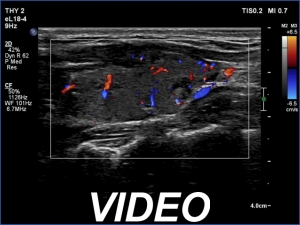

Ultrasonography. The thyroid was minimally hypoechoic and had several deeply hypoechoic discrete lesions. The latter had irregular margins and corresponded to more active foci of thyroiditis.